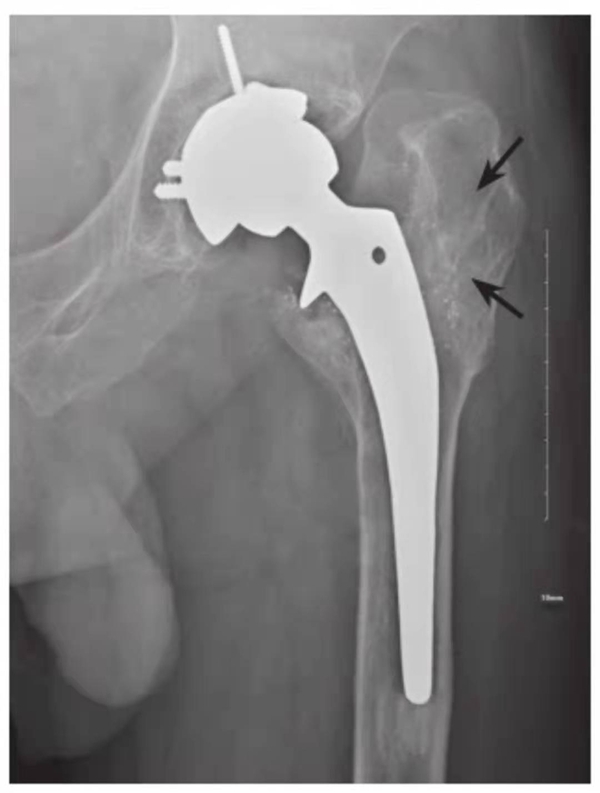

图4 右侧人工髋关节置换术后感染并松动

女性,89岁。发现右大腿中段后侧流脓2个月余。平片,示右股骨上段骨密度增高,内侧骨膜增生,假体周围骨质吸收,髋臼杯内陷,人工股骨柄部内移